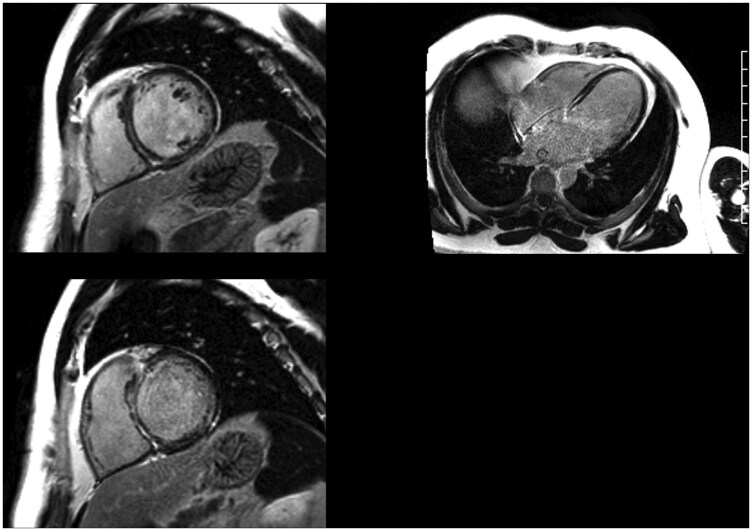

Case summary: An asymptomatic 47-year-old man presented to cardiology clinic for smartwatch low-rate alarms. His brother had exertional syncope and died in his 20s from heart failure. Transthoracic echocardiogram showed reduced left ventricular ejection fraction (35%). A Holter monitor showed third-degree atrioventricular block and frequent pauses (longest 4.9 s). He was admitted to the hospital and following a cardiac magnetic resonance imaging with late gadolinium enhancement a cardiac resynchronization therapy-defibrillator was placed. Genetic testing identified a pathogenic variant in the lamins protein A and C (LMNA) gene.

Abstract Image